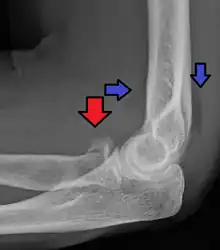

Radial head fracture (red arrow) with posterior and anterior sail sign (blue arrows)

Radial head fractures are diagnosed from a clinical assessment and diagnostic imaging. Clinical assessment may include pain or tenderness at the radial head, bruising, swelling, and a limited range of motion of the injured elbow.[2] Diagnostic imaging may include ultrasound, plain radiography (x-ray imaging), Computed tomography scan (CT), and magnetic resonance imaging (MRI).[2][4] A fat pad sign may be present on diagnostic imaging and may indicate a radial head fracture.[5]